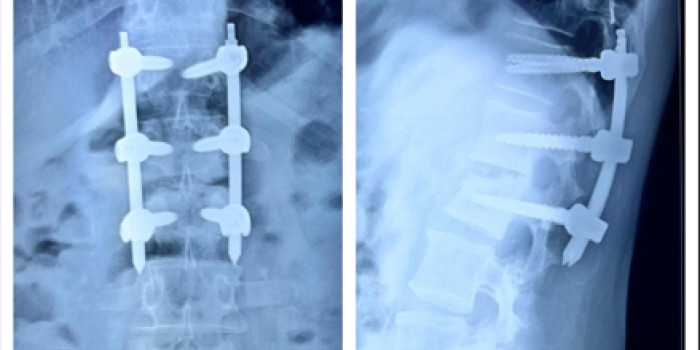

• Disc Herniation – Discectomy / Fusion Surgery

• Spinal Trauma – Fractures

• Revision Spine Surgery